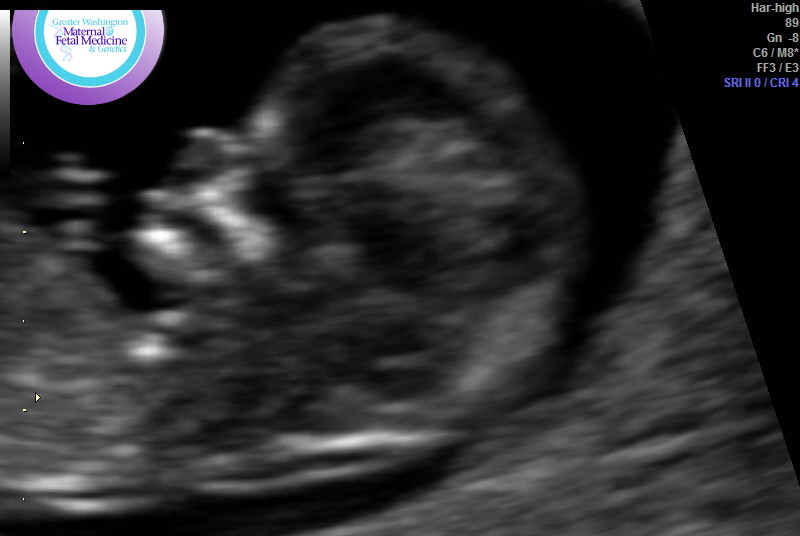

Here are the nub/skull pics again:

Attachment 41115Attachment 41116Attachment 41117Attachment 41118Attachment 41119